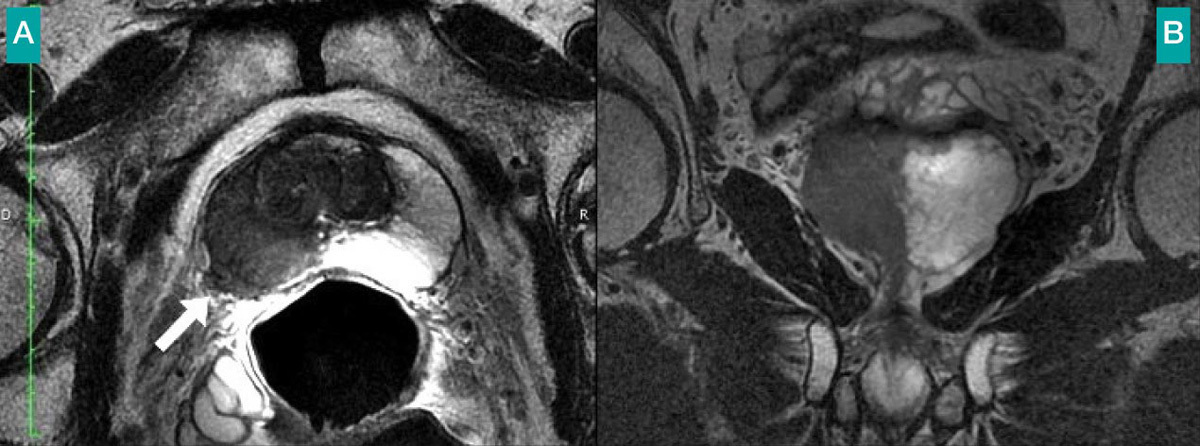

Patient de 68 ans adressé pour bilan d'extension d'un cancer de la prostate, PSA à 12,5 ng/mL.Le toucher rectal trouve une induration du lobe droit de stade clinique T2. L'imagerie par résonance magnétique montre une large plage en hyposignal en T2 de tout le lobe droit. Surtout, il existe une effraction capsulaire signant un stade T3